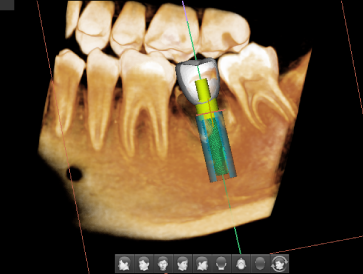

В комплекте с данным аппаратом Вы приобретаете 5 лицензий программного обеспечения EzDent-i со встроенным планировщиком имплантов

- 5 лицензий ПО EzDent-i - Программа для получения, обработки, хранения и экспорта рентгеновских исследований.

- 5 лицензии ПО Ez3D-i - Программное обеспечение для 3D диагностики и планирования имплантации, включающая в себя следующие элементы: